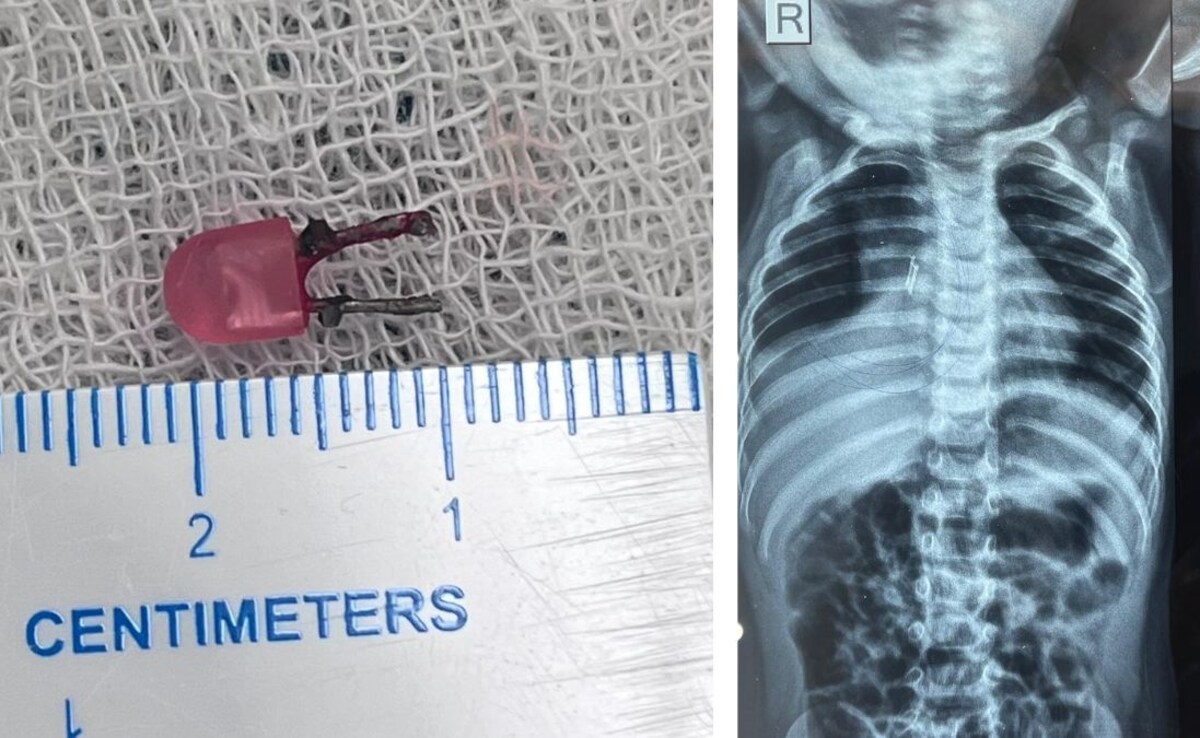

14 महीने की बच्ची के गले में फंस गई थी आधा इंच चौड़ी स्प्रिंग, एम्स के डॉक्टरों ने ऐसे किया चमत्कार

नई दिल्ली: अगर किसी मासूम के खाने की नली में स्प्रिंग फंस जाए तो सोचिये वो कितनी गंभीर स्थिति में होगी. उसकी जान भी जा सकती है लेकिन नई दिल्ली स्थिति एम्स के डॉक्टरों ऐसी ही एक 14 माह के नवजात बच्ची का सफल इलाज कर जान बचाई है.

खेल-खेल में निगल गया LED बल्ब, डॉक्टरों ने ऑपरेशन से ऐसे बचाई मासूम की जान,देखें VIDEO